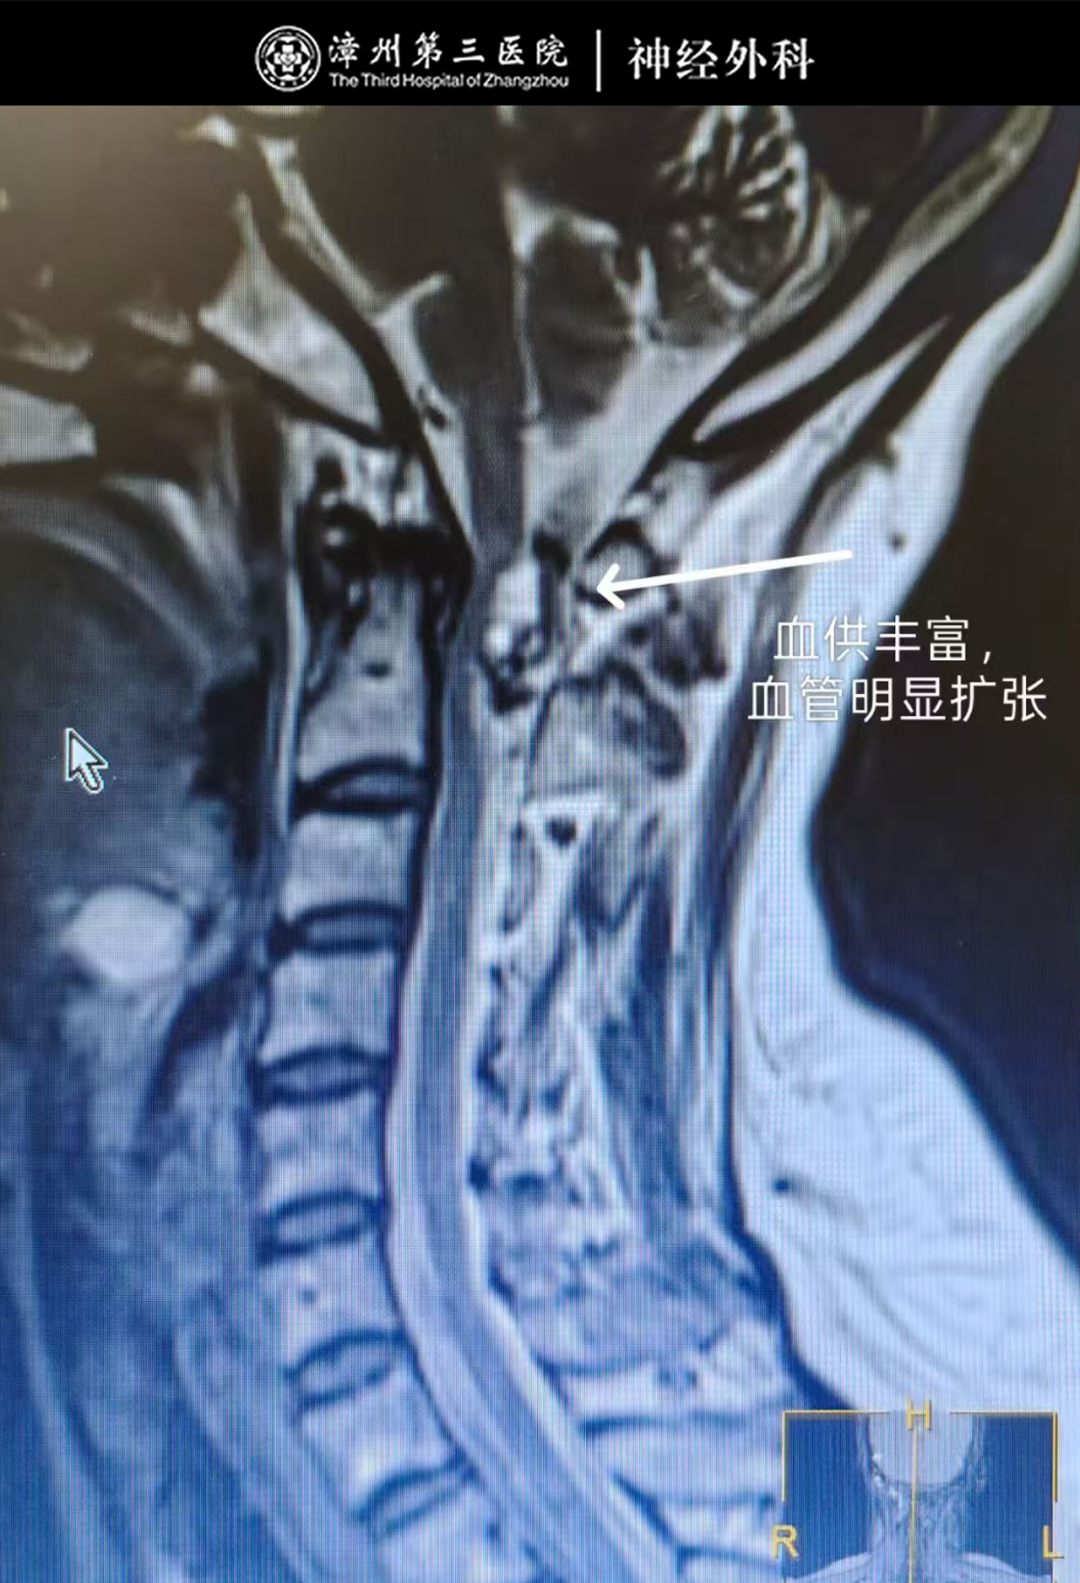

结合颈椎CT显示的C1-2椎体水平椎管内占位性病变特征、颈椎MR增强检查的精准定位,以及患者反复颈痛的临床症状,团队明确需手术切除占位组织以解除脊髓压迫、根除颈痛,且术后可通过病理检查明确占位性质,为康复提供依据。因手术部位邻近重要神经血管,难度与精度要求高,漳州第三医院副院长、神经外科专家林友城牵头制定“显微镜下C1-2硬膜下髓外占位切除术+神经根粘连松解术”个性化方案。